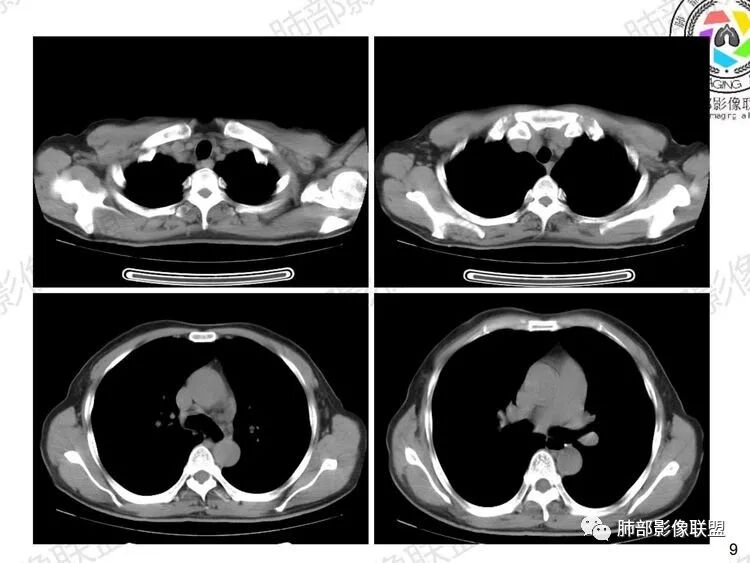

影像表现:

1、双肺从中心向外周对称性弥漫分布的磨玻璃密度影,无重力分布特点

2、中内带分布为主,胸膜下较少受累,可见月弓征

3、下肺纤维灶形成

结合患者症状典型的呼吸困难症状及影像学改变,临床症状轻,影像重,双肺从中心向外周对称性弥漫分布的磨玻璃影,无重力分布,胸膜下受累不明显(月弓征),呈典型的间质性改变,需要考虑肺孢子菌肺炎的可能,临床上需要结合有无HIV、使用免疫抑制剂病史、器官移植等免疫缺陷病史,还可以借助化验CD4细胞、LDH等进一步判断病情。